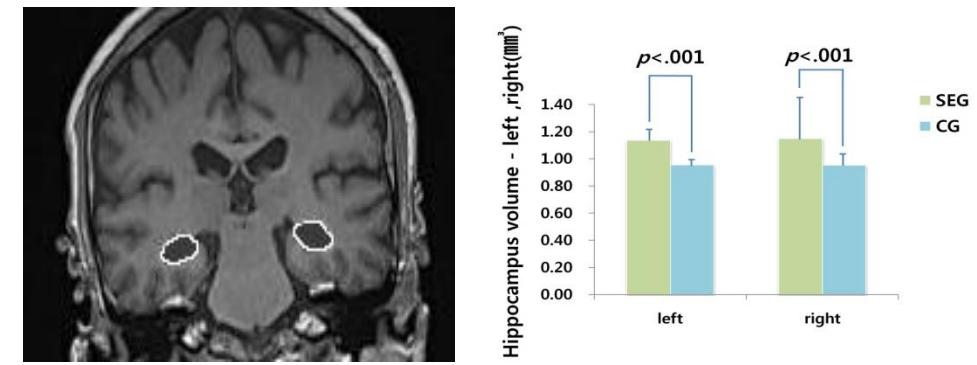

海马体就是最能从长期运动中受益的脑区之一。在一项研究中,参与者在 12 个月的有氧锻炼后,海马体的体积增加了 2%,还有多项研究也观察到了类似的现象。

经过24周力量训练后,运动组(右图中浅绿色)的左、右海马体积均显著大于对照组(右图中蓝色) 图片来源:文献[7]海马体是大脑的「记忆中心」,我们的短期记忆、长期记忆和空间认知能力,都属于海马体的「业务范围」。更大的海马体体积,与更强的记忆力和认知功能十分相关。